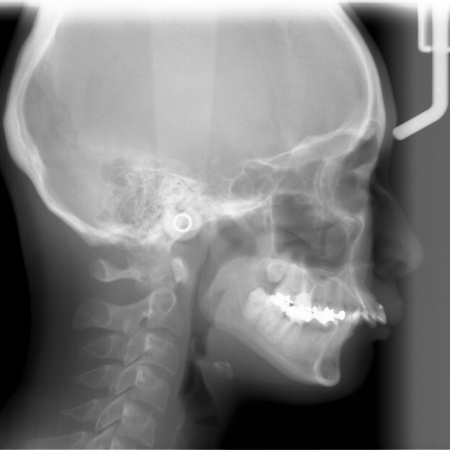

レントゲン撮影をして詳しく調べた結果、歯の位置だけでなく、骨格的な問題があることが分かりました。

患者様の場合、骨格的な上顎前突が噛み合わせを乱している主な原因であることから、矯正治療では前歯を後方へ大きく動かすためのスペースを確保する必要があります。

上顎の奥歯(第1小臼歯)を左右1本ずつ抜き、奥歯にアンカースクリューを埋め込みます。上奥歯をしっかりと固定することで、抜歯で確保したスペースを最大限に活用しながら、前歯を効率よく後方へ牽引することが可能です。